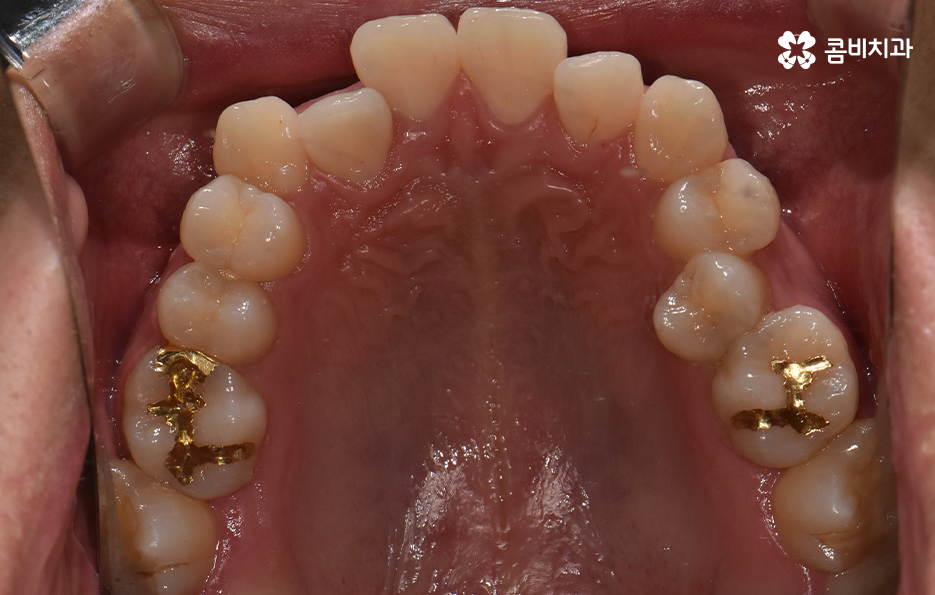

오늘 포스팅에서 보여지는 사진에서는 비발치 교정으로 덧니 교정이 가능했던 사례입니다. 덧니 교정 사례에서 발치교정 케이스는 흔한 치료 방법이긴 하지만 발치에 대한 판단은 치열만이 아니라 골격과 얼굴형을 종합적으로 고려하여 판단하고 치아를 얼마나 이동시켜야 할지 예측하여 판단하기 때문에 3D CT 등의 첨단 장비를 통한 검진과 경험 많은 교정 전문의와 충분히 상의하고 결정해야 합니다

치아교정은 치열을 가지런하게 재배열하는 치료이면서 각 개인의 얼굴형과 골격, 입술라인 등을 종합적으로 고려해야 하기 때문에 발치교정의 필요 여부를 판단하는 것에도 신중한 판단이 필요한데요

30대 치아교정 되도록 빨리 치료가 끝나길 원하시는 분들이 많겠지만 교정 치료는 결과가 중요한 치료이기 때문에 자신에게 적합한 치료 계획을 정교하게 세우는 것이 중요하며 발치는 한번 하면 되돌릴 수 없고 반대로 비발치 교정을 한다고 해도 치료상의 편의성만을 따지는 것이 아니라 결과가 중요하기 때문에 각 환자분들의 얼굴에 잘 어울리는 결과를 얻기 위해서는 비발치 교정이 얼마나 적합한지를 잘 따져봐야 하겠습니다

종합하면 발치교정의 필요성은 얼굴과의 조화, 골격 그리고 교합 등을 전체적으로 고려하여 판단하기 때문에 각 환자분들이 필요한 치아의 이동 정도를 정확히 예측하고 필요한 치아 이동 공간을 확보함에 있어서 발치교정이 적합할지 아니면 비발치적인 방법으로도 치아 이동 공간이 확보 가능한지 따져보고 있으며 발치교정이 아니더라도 치간삭제, 악궁확장, 어금니 후방이동과 같은 방법으로 공간 확보가 가능하기 때문에 각 환자분들에게 적합한 1:1 맞춤형 치료가 진행되고 있어요